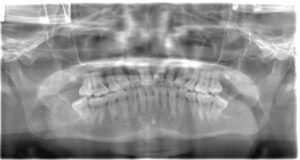

奥歯の近くには神経が通っているため、特に下顎の抜歯では神経損傷のリスクが伴います。これを防ぐため、CTスキャンなどで事前に精密な位置確認を行い、安全に治療を進めるためのプランを立てます。